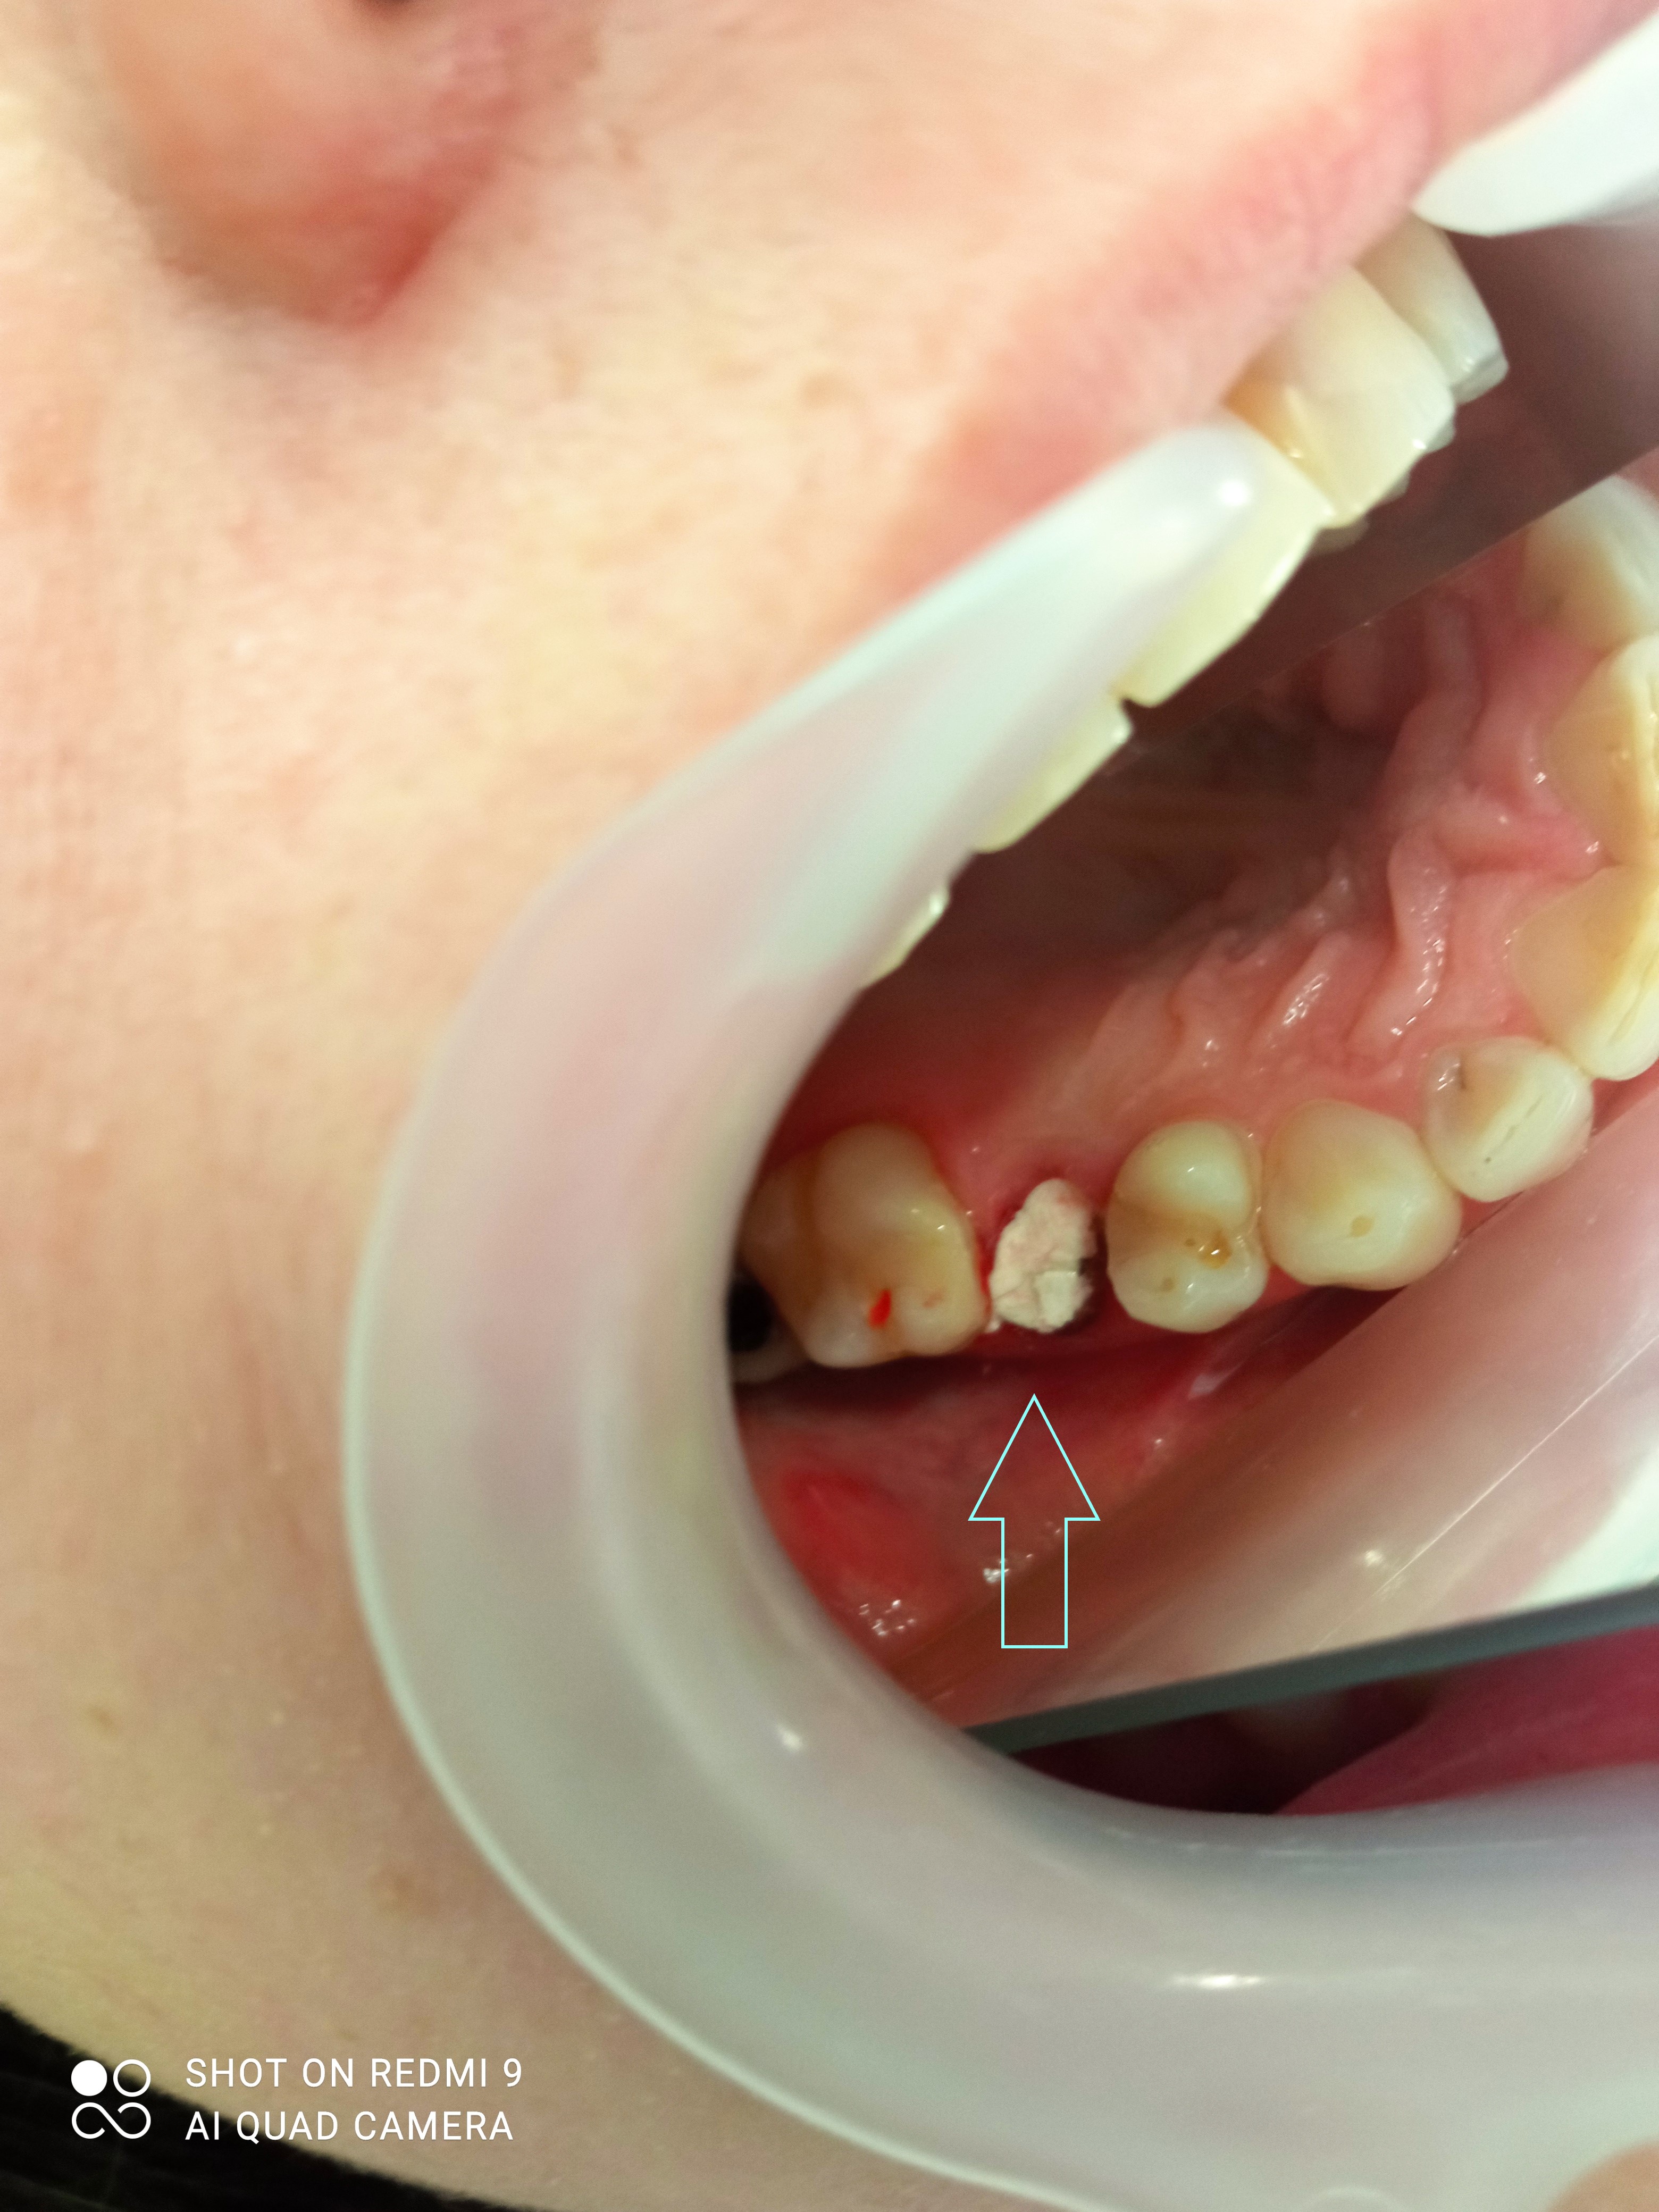

Ο πρώτος γόμφιος στην αριστερή πλευρά της κάτω γνάθου είχε απονευρωθεί στο παρελθόν. Ο ασθενής δεν θέλησε να καλύψει το δόντι με θήκη, ώστε να είναι πλήρως προστατευμένο με αποτέλεσμα το δόντι να σπάσει (όπως φαίνεται στην αρχική εικόνα). Η λύση θεραπείας ήταν η κατασκευή στεφάνης δοντιού, αφού προηγουμένως το δόντι τροχίστηκε καταλλήλως και ο οδοντοτεχνίτης κατασκεύασε την ολοκεραμική θήκη ζιρκονίου.

Το δόντι είναι πλέον πλήρως προστατευμένο και μπορεί να αντέξει στο πέρασμα των χρόνων.

ΠΡΙΝ

ΜΕΤΑ